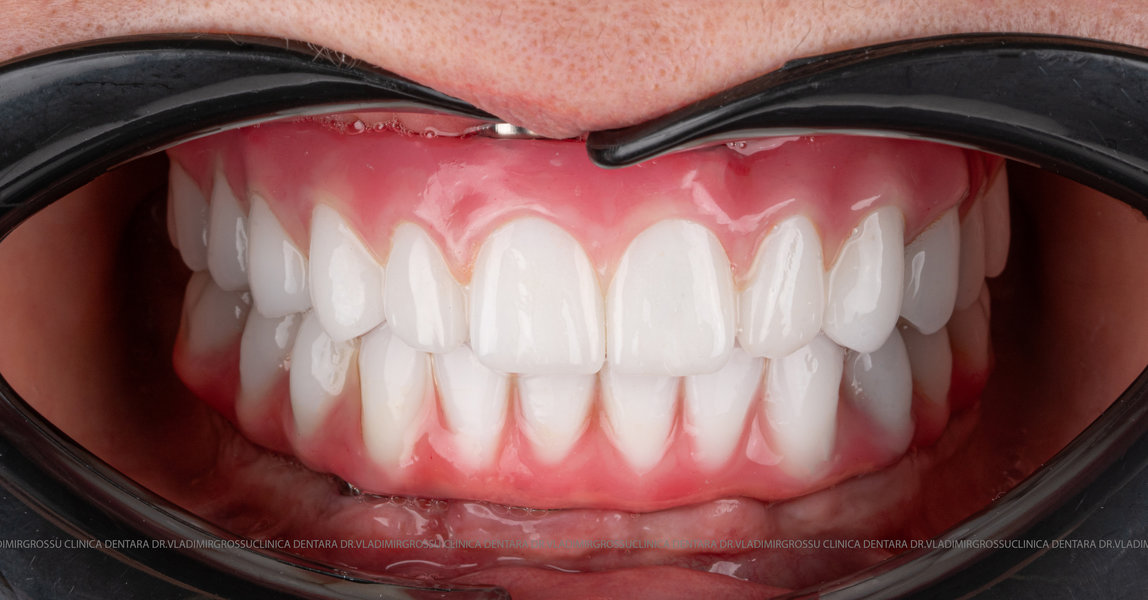

- A doua etapă are loc la aproximativ 6 luni după intervenție, când se realizează proteza definitivă, care este fixată pe implanturi prin intermediul unor piese numite multiunit-uri. Această etapă presupune lucrul la nivelul multiunit-urilor, nu direct pe implanturi, reducând astfel riscul de complicații.

Caz 2

- Posibilitatea realizării unei proteze cu 12-14 dinți, oferind un aspect estetic natural și funcționalitate optimă.

- Proteză definitivă realizată din metaloceramică sau zirconiu, cu 12-14 unități (soluția recomandată).